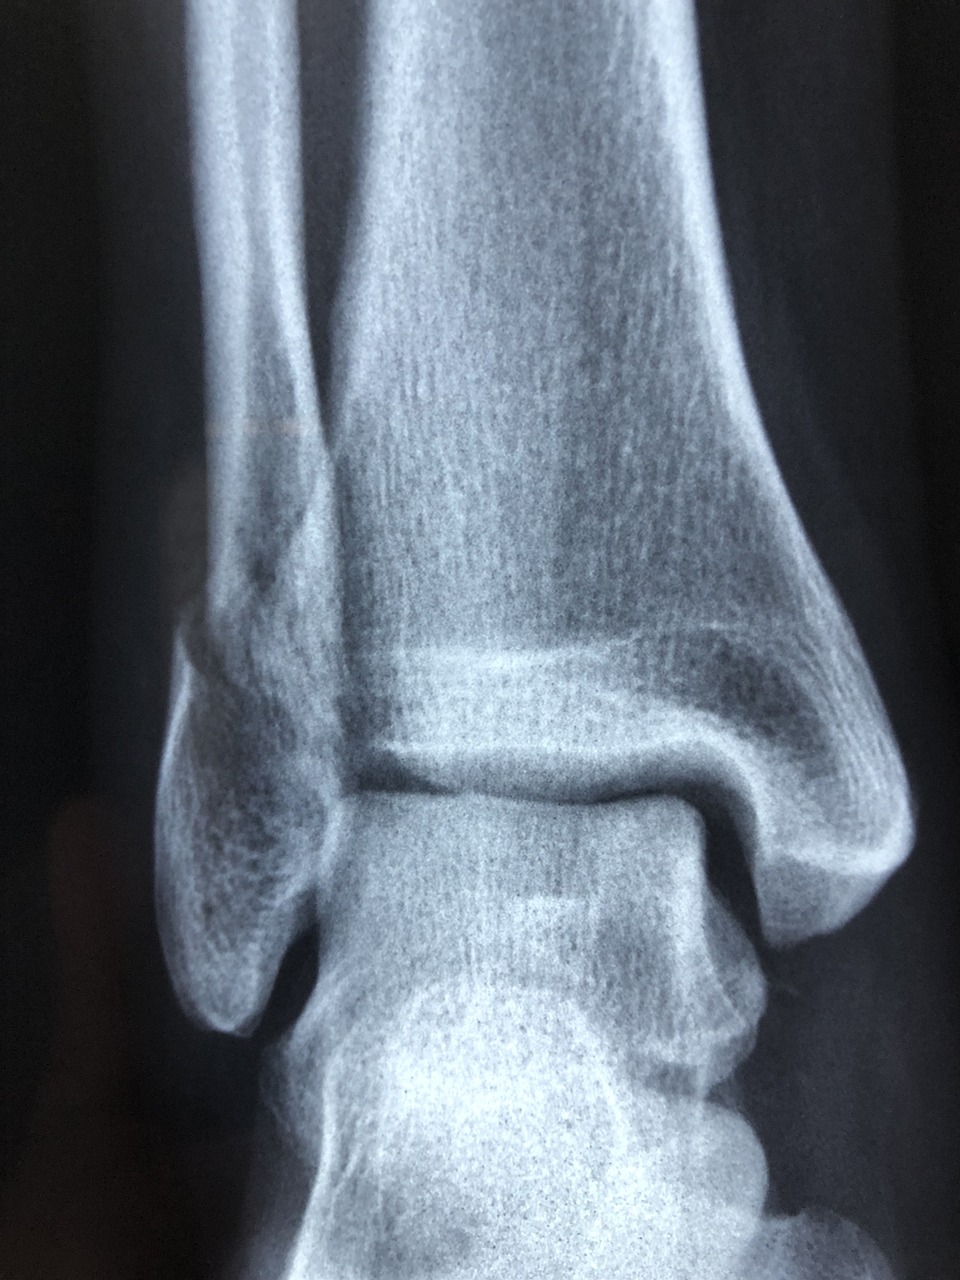

엘보 통증은 골프 중 뒷땅을 치며 손목과 팔꿈치에 강한 충격이 전달되면서 발생하는 손상입니다. 특히 ‘골프 엘보’로 불리는 이 증상은 내측 상과염(Medial Epicondylitis)으로, 팔꿈치 안쪽 힘줄이 과도한 사용이나 반복된 충격으로 인해 염증이 생긴 상태를 말합니다. 뒷땅을 칠 때 클럽 헤드가 지면에 부딪히면서 발생하는 반동은 손목을 거쳐 팔꿈치까지 전달되며, 이때 팔꿈치 내측의 굴곡근이 손상을 입게 됩니다.